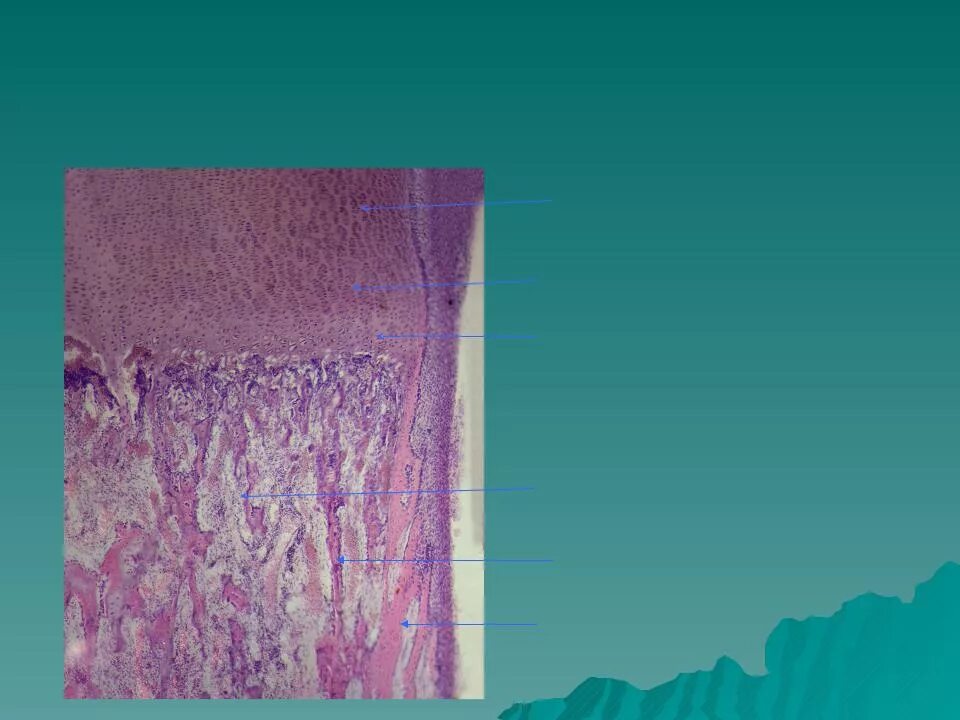

Развитие хряща гистология